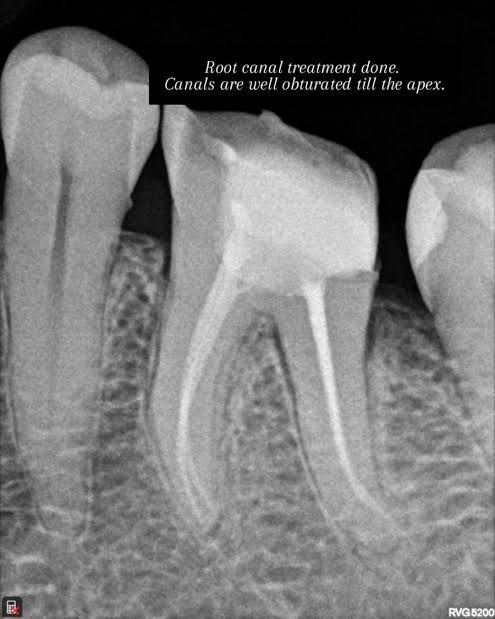

Root canal treatment is a dental procedure that saves and restores a severely infected or damaged tooth...